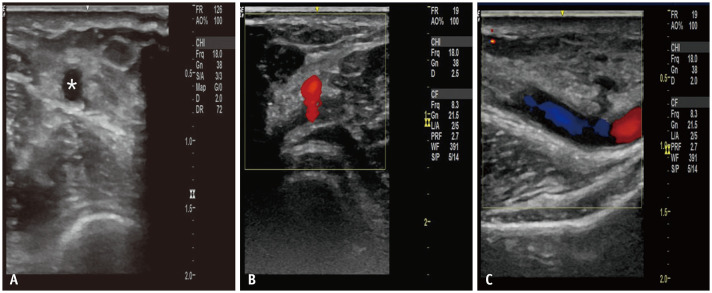

Abstract Image